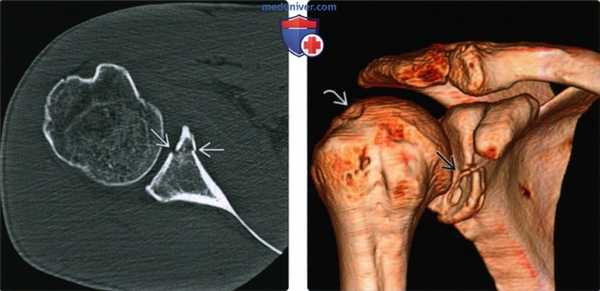

(Слева) Осевая КТ, пациент с ранее вправленным вывихом, которого сейчас беспокоит передняя нестабильность и боль. Имеется перелом Банкарта переднего края суставной впадины КТ позволяет оценить перелом Банкарта, который не виден на рентгенограмме и помогает при дооперационном планировании.

(Справа) На передне-задней 3D КТ у этого же пациента определяется перелом Банкарта передненижнего края суставной впадины. У пациента также имеется небольшой вдавленный перелом Хилла-Сакса заднелатеральной верхней области головки плечевой кости.

3. КТ при переднем вывихе плеча:

• После вправления: более чувствительная при демонстрации переломов Хилла-Сакса и Банкарта, чем рентгенография:

о При большом переломе Хилла-Сакса и рецидивирующем вывихе: помогает планировать операцию с костным трансплантатом

о Потеря участка кости суставной впадины или большой перелом Банкарта: помогает планировать вмешательство Бристоу-Латарьета